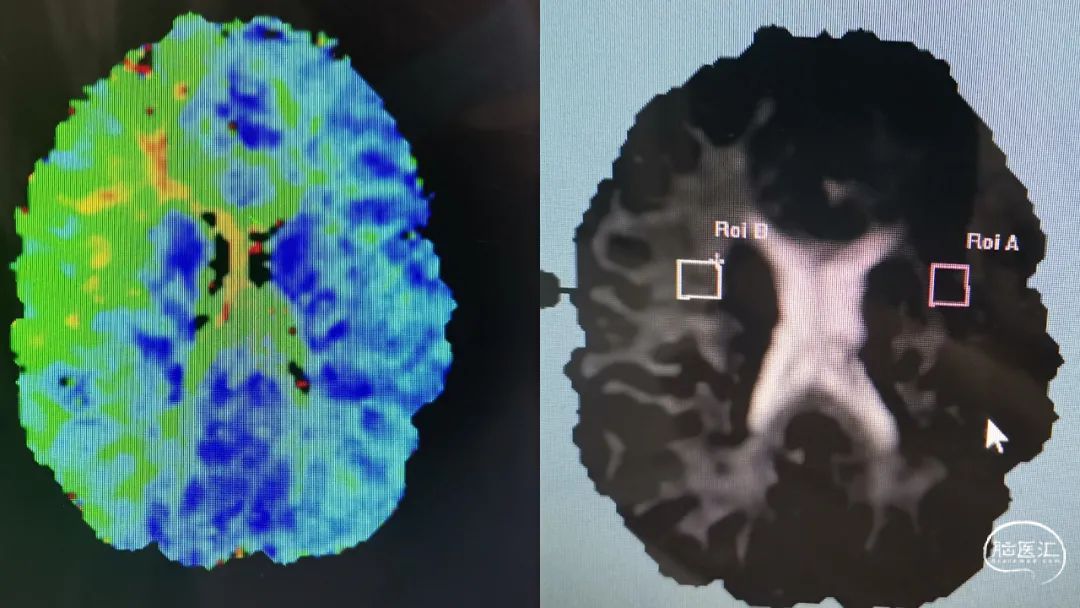

MRI显示右侧基底节区梗死缺血灶。

DWI显示右侧低灌注。